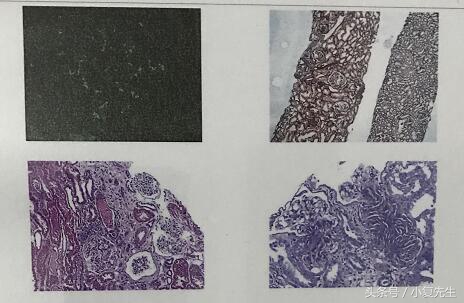

在慢性肾脏疾病病理诊断中一般常见有五种病理诊断,局灶节段性肾小球硬化症【FSGS】是其中之一,其主要病理表现为部分肾小球及部分肾小球毛细血管襻发生硬化性改变,近年来又根据光镜下的特点,把它细分为门周型、细胞型、顶端型、塌陷型和非其他类型几种亚型,各型的临床表现、对治疗的反应和预后都有所不同。局灶节段性肾小球硬化可以是原发性的,也可以继发于某些全身性疾病(称为继发性局灶阶段性肾小球硬化),一般所说的局灶节段性肾小球硬化症指的是原发性的,它是一种免疫异常所致的疾病。

本病的确诊依靠肾穿刺病理学检查,但肾穿刺检査不能很好地区分是原发性还是继发性,原发性和继发性局灶节段性肾小球硬化症的鉴别往往需根据病史、肾脏以外表现等。继发性局灶节段性肾小球硬化症的治疗方法与原发性者迥异,所以对任何一例诊断为局灶节段性肾小球硬化症的患者,都应仔细排除继发性者。

诊断要点:确诊有赖于肾活检病理诊断。